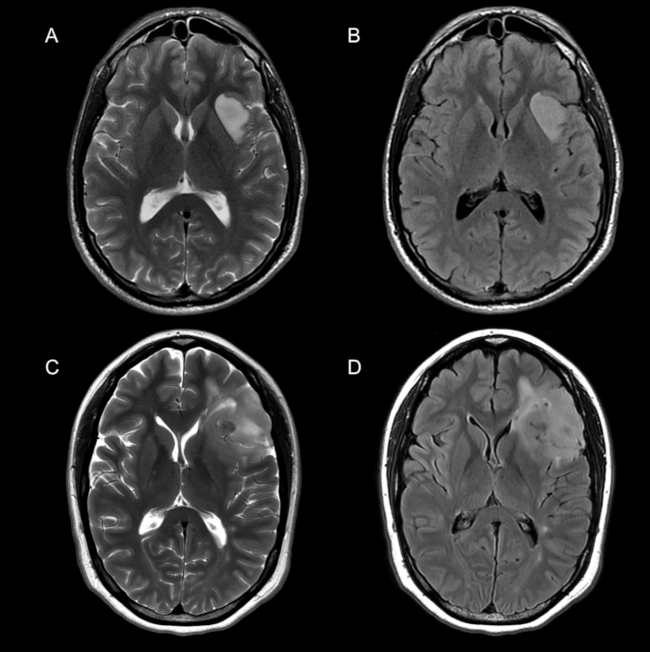

La ►Figura 2 ejemplifica las características por imágenes en relación a la valoración de los bordes y la señal en un paciente 1p/19q no codelecionado (A, B) y codelecionado (C, D).

En la valoración de los bordes, se clasificaron como netos aquellos tumores en los cuales la interfaz entre el tumor y el parénquima normal pudiera ser delimitada perfectamente. En caso contrario fueron asignados como difusos.

La señal tumoral fue valorada en secuencias ponderadas en T2, siendo heterogéneos aquellos tumores que mostraron dos o más intensidades de señal intralesionales. De lo contrario, aquellos tumores que demostraron una única intensidad de señal fueron clasificados como homogéneos.